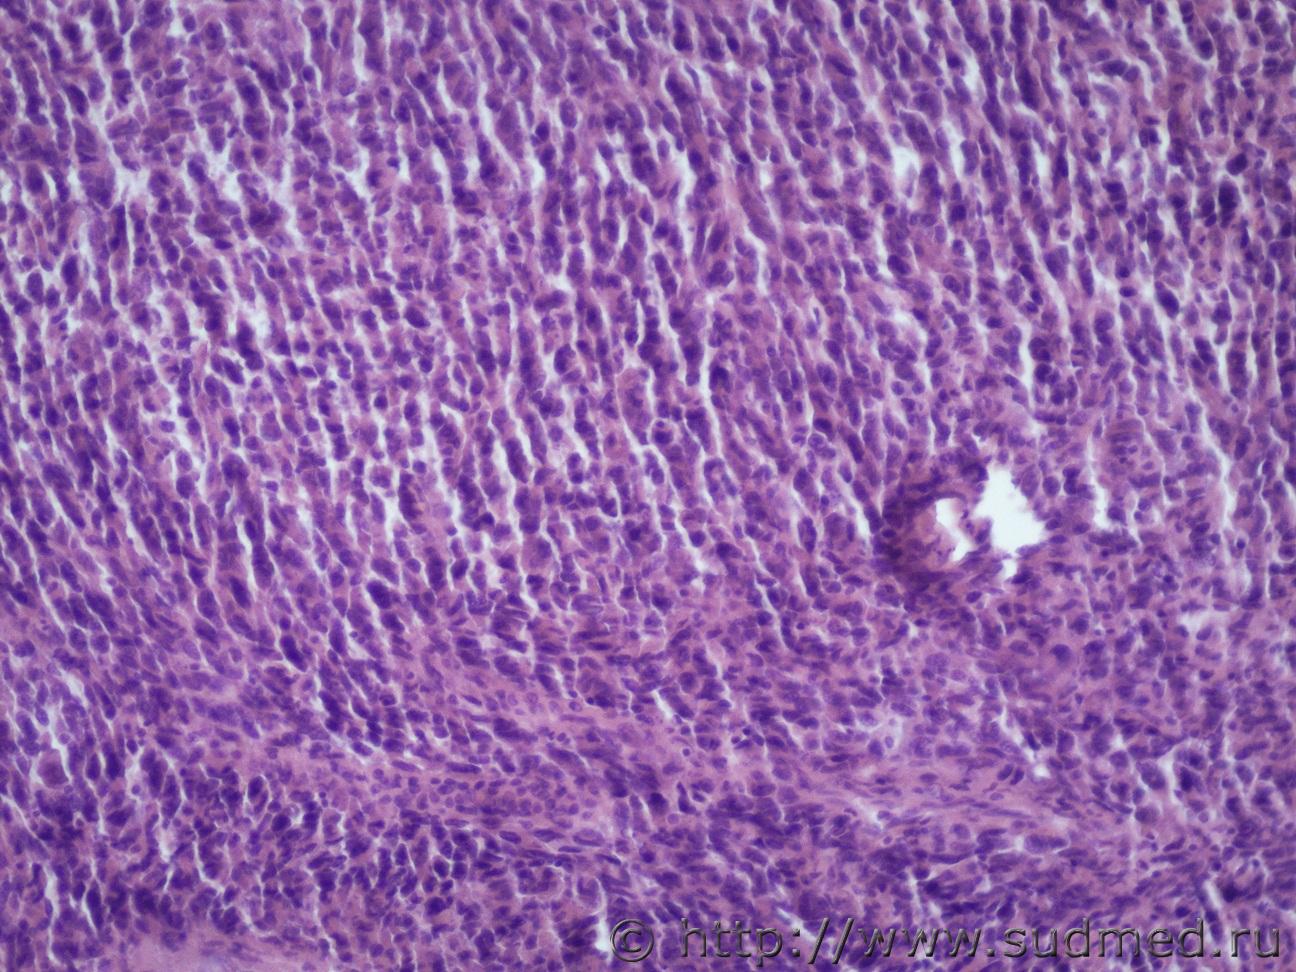

Ув. коллеги доброго дня. Представляю опухоль мочки пр. ушной раковины (9х5х4 см).Судебная медицина - Прикрепленное изображение Судебная медицина - Прикрепленное изображениеСудебная медицина - Прикрепленное изображениеСудебная медицина - Прикрепленное изображениеСудебная медицина - Прикрепленное изображение

Первое,что приходит на ум - это меланома,но надо ещё deal1.gif .

Соглашусь с ув. Медиком. Тоже подумал в первую очередь о меланоме.

Похоже на гигантскую ювенильную ксантогранулему.

Чем ?

Не вижу ксантомных клеток и эозинофилов.

Ювенильная ксантогранулёма встречается главным образом у детей,а в консультируемом случае,скорее всего, умерший недетского возраста.

Да, возраст 65 лет

Тогда соответствует картине Атипической фиброксантоме(AFX)